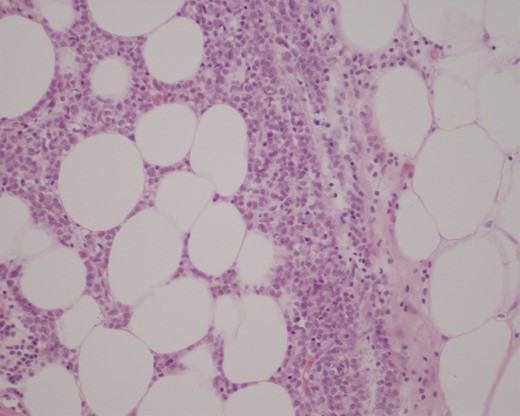

Histopathological examination of the resected specimens showed a 3-cm intraluminal gallstone within the proximal ileum, with focal metastatic carcinoma consistent with breast primary present in the adjacent mesenteric adipose tissue (Fig. 3), while the more distal, strictured ileal segment revealed mucosal and transmural involvement by metastatic breast carcinoma (Fig. 4). The tumour cells were strongly positive for cytokeratin, oestrogen receptor and focal progesterone receptor (<5%), consistent with metastatic breast carcinoma. They also displayed a mixed ductal and lobular differentiation pattern.

Immunohistochemical stain of distal ileal resection showing an extensive transmural involvement by metastatic carcinoma (×200).